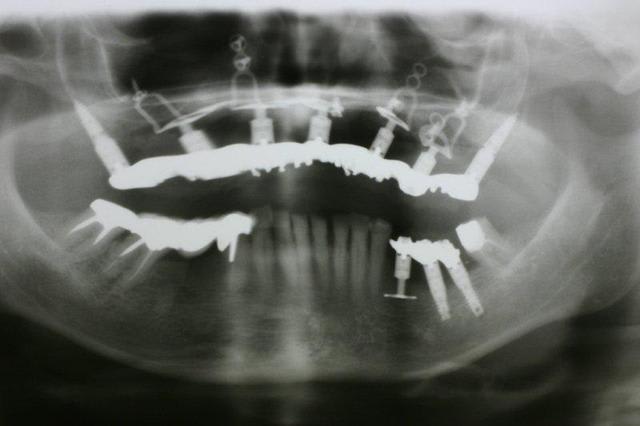

Pépé a inventé le All on Seven...))))

Pcq ds ces cas là onne sait pas faire autrement

Mais je te signale qd même que

1. les palques ont une assisse énorme par rapport à 7 cylindres

2. la résorption centripède du maxillaire le rend trop petit pour en poser plus

De plus malgré le grand overjet , on a qd même un implant central qui soutient l arc incisif, même s il est 2 cm en arrière de la ligne des dents

Pp peux tu nous en dire plus sur l'aspect de la gencive qui entoure le disk le plus antérieur?

Pas le disk antérieur mais le disk et les 2 plaques antérieures pour être plus exact

La rougeur au fond du vestibule est due au frottement de la fausse gencive contre la partie libre muqueuse...

Vouspourriez dire que je suis ds la merde car la difficulté d accès à l hygiène ds cette zone a provoqué cette inflammation qui serait préjudiciable aux implants...

Et bien je répondrais oui et non

OUI j ai eu les boules en voyant cette muqueuse gonfler au fil des mois car j ai cru que l inflammation alllait avoir raison de mes plaques...

NON pcq la prolifération de la muqueuse n est finalement pas due au manque d hygiène possible à cet endroit mais bien au fait d avoir utilisé un matériau de comblement effciace qui donne du vrai os et sur ce vrai os on retrouve de la gencive attachée, rose, ferme, soutenue et vascularisée...gencive qui prolifère au point de comprimer la fauuse gencive et la pas la fausse gencive qui comprime la muqueuse...

Mais si j avais fait la même chose avec de l INTERPORE , matériau corralien non résorbable, non seulement je n auaris pas obtenu de l os mais alors l inflammation aurait été réelle et aurait mis en péril mon implanto...

Pp

ne crois tu pas qu'il s'agisse plus tôt d'un phénomène diapneusique sous "l'overjet" de ta prothèse.

et que l'inflammation induite finira par avoir la peau des plaques?